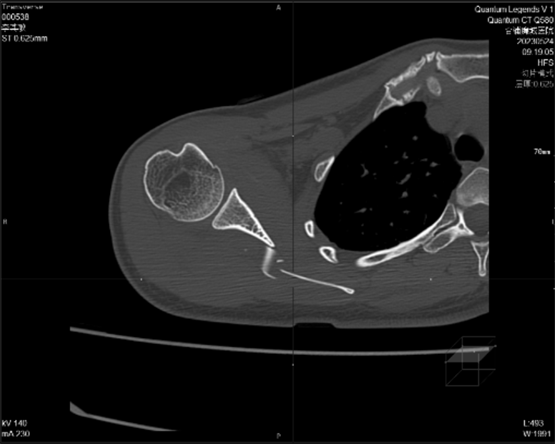

宽腾64排128层CT目前在该院主要使用方向和情况为常规平扫加增强,体检为后续发展主要应用方向;急诊以外伤为主,现阶段重点以下肢造影偏多,检查人群以老年人为主,现阶段每日扫描量为15左右,目前该设备在当地的先进度仅次于人民医院中医院。

2.急诊以外伤为主:宽腾医疗CT系列采用大孔径设计,急诊外伤患者等特殊体位患者更大包容性,一站式急诊扫描流程,智能摆位,一键建档,最快0.5秒机架旋转,同台多平面重组/3D多序列多算法重建图像,为医生争取抢救黄金时间。

目前,通过对当地其他医院的CT和现已装机的64排128层螺旋CT图像质量进行对比分析发现,两者在扫描范围上有很大差异,这对于提高临床医生对疾病的认识和诊治水平有着十分重要的意义;另外,其相对于普通设备而言具有更大的体量优势和功能优势,使得它能够满足不同病人的需求。同时,对心脏成像、脑血管综合解决方案、血管成像、肺结节检查及结肠病变普查等多项科研技术实现了重大突破。